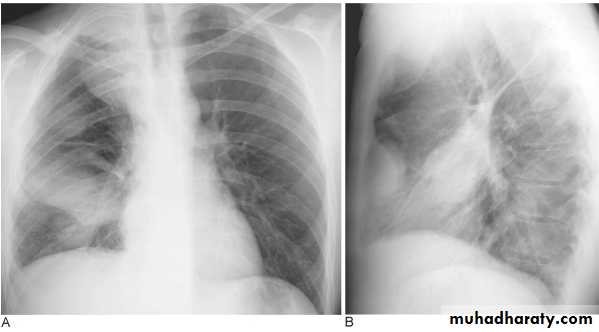

Pleural Effusion on Chest Radiographs.

Posteroanterior (A) and lateral (B) chest radiographs demonstrate the typical meniscoid appearance (arrows) in a patient with a left pleural effusion